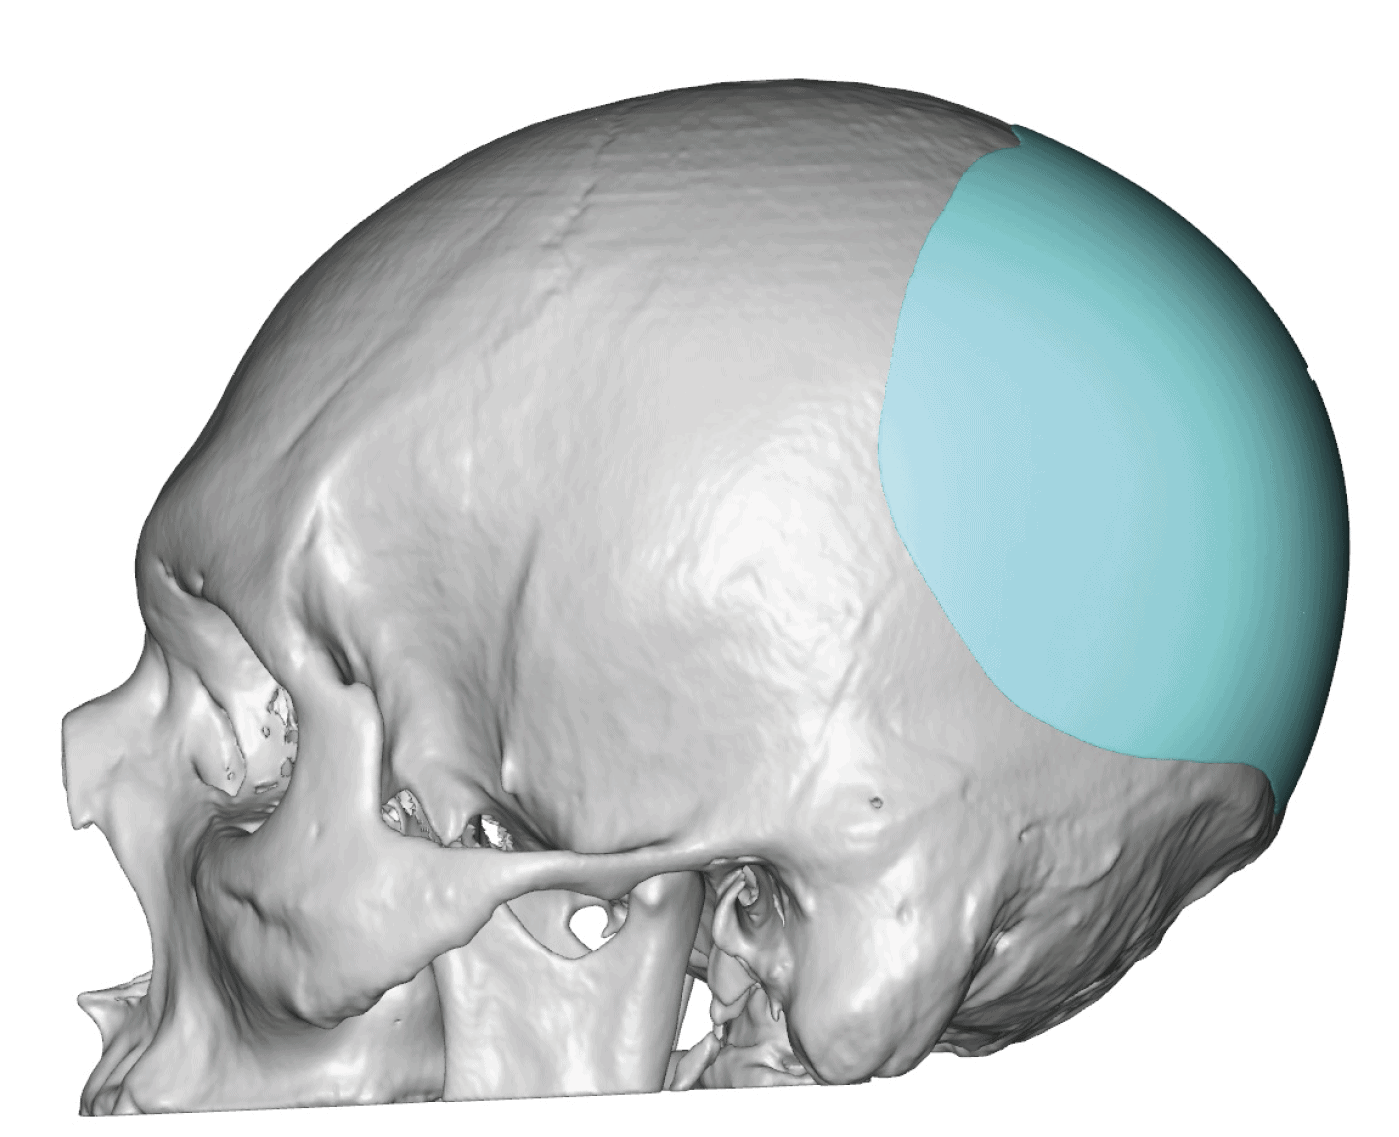

Patient 28

Desire for rounder shape to the top of the head from a congenital parasagittal deficiency skull shape.

Custom skull implant designed to fill in the parasagittal deficiencies.

Desire for rounder shape to the top of the head from a congenital parasagittal deficiency skull shape.

Custom skull implant designed to fill in the parasagittal deficiencies.